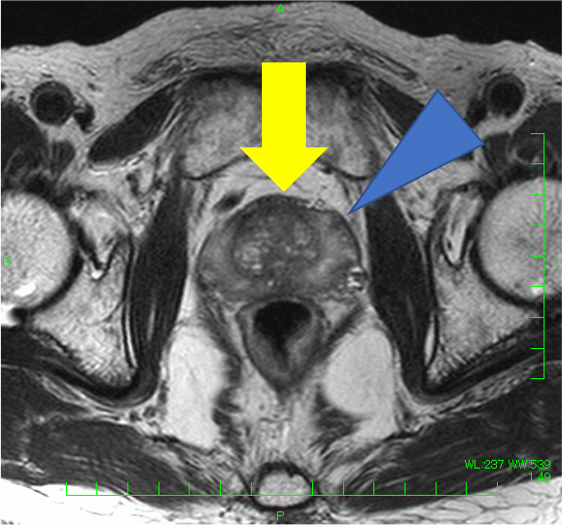

検診でPSA 4.9と上昇があり、MRIが施行された。左移行域に14mmの病変を認め、T2強調像で低信号(PI-RADS v2.1スコア4)、拡散強調像で高信号・Appar-ent Diffusion Coefficient(ADC)低下(スコア4)、ダイナミックで早期濃染を示し、PI-RADS v2.1でカテゴリー4と判定され前立腺癌が疑われた。一方、辺縁域はT2強調像で不均一低信号を呈したが、結節様の拡散強調像での強い高信号、ADC低下はなく、ダイナミックMRIでも結節様の早期濃染はなく、びまん性遷延性の染まりがみられたことから炎症性変化と判断した。生検が行われ、癌の診断であった。その後、ロボット支援下根治的前立腺摘除術が施行され、MRIと一致した前立腺癌の診断を得た(Gleason score 4+3=7, pT2N0)。

本症例では、左移行域腹側の病変(14mm、T2強調像:低信号(スコア4)、拡散強調像:高信号・ADC:低下(スコア4)、ダイナミック:早期濃染: PI-RADS v2.1カテゴリー4)は、前立腺癌の判定が容易であった。一方、辺縁域はT2強調像でびまん性に不均一な低信号を呈し、癌の評価が難しい方であった。左辺縁域に小結節様のT2強調像にて低信号がみられ、拡散強調像やADCの所見は明瞭でなく癌の可能性は低いと考えたが、T2強調像での信号が明瞭で、癌を否定してよいのか悩ましい。本症例では、ダイナミックMRIも施行しており、左移行域腹側病変は早期濃染―washout パターンを呈したが、左辺縁域の小結節に早期濃染はなく、両側辺縁域とも遷延性の染まりを認めたため、辺縁域に癌はなく、両側辺縁域に炎症性変化があると断定できた。病理的にも、MRIで指摘した病変部のみ癌が同定され、その他の領域に癌はなかった。